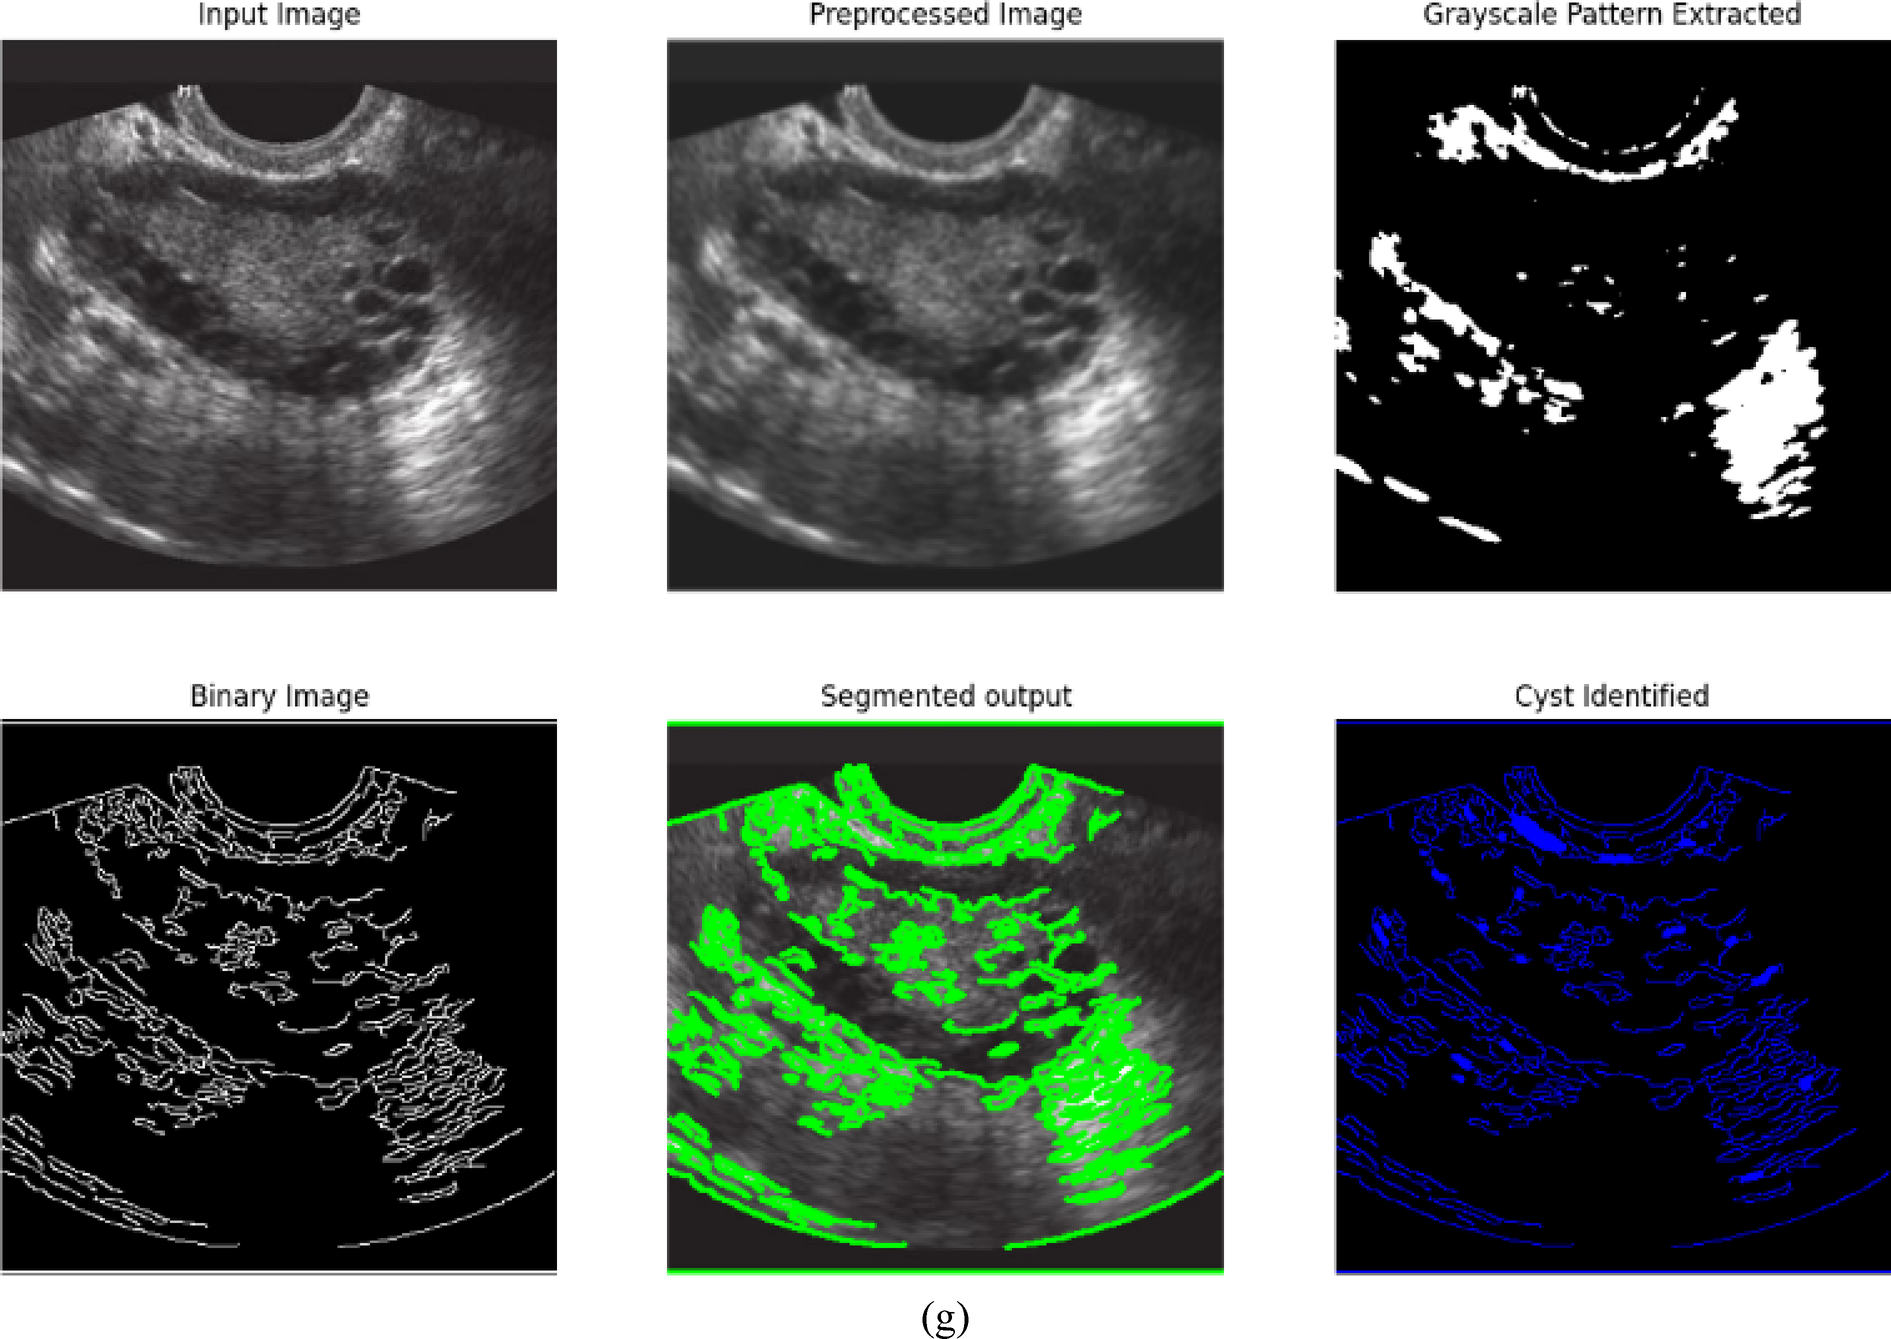

From: Advanced holographic convolutional dense networks and Tangent runner optimization for enhanced polycystic ovarian disease classification

Sample input and output images of Kaggle PCOD image dataset.